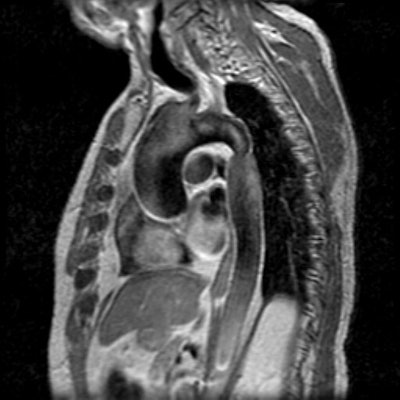

Post stenotic aortic dilatation

There is dilatation of the ascending aorta shown on the MR images below. The sinotubular junction is not affected. Flow void within the ascending aorta on flow images is related to turbulent flow associated with the stenotic aortic valve. The patient also has a coartation of the descending aorta. Turbulent flow void can be seen at the site of coarctation. About 50% of patients with aortic coarctation have a bicuspid aortic valve which can prematurely degenerate.